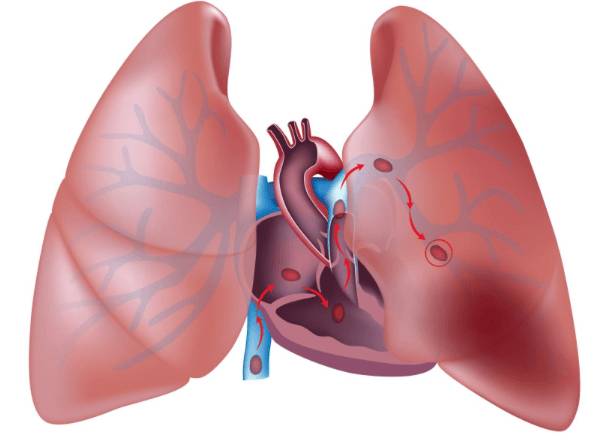

Тромб, который приводит к тромбоэмболии, может образовываться в ногах, в правом отделе сердца. При отрыве он поступает в малый круг кровообращения и движется по лёгочной артерии.

Если он отрывается, то перекрывает ветви артерии, блокирует кровоток, что нередко приводит к смерти пациента.

Последствия зависят от размеров сгустка и локализации закупорки. Путешествующий тромб в лёгочной артерии нарушает кровообращение, вызывает кислородное голодание и гипоксию.